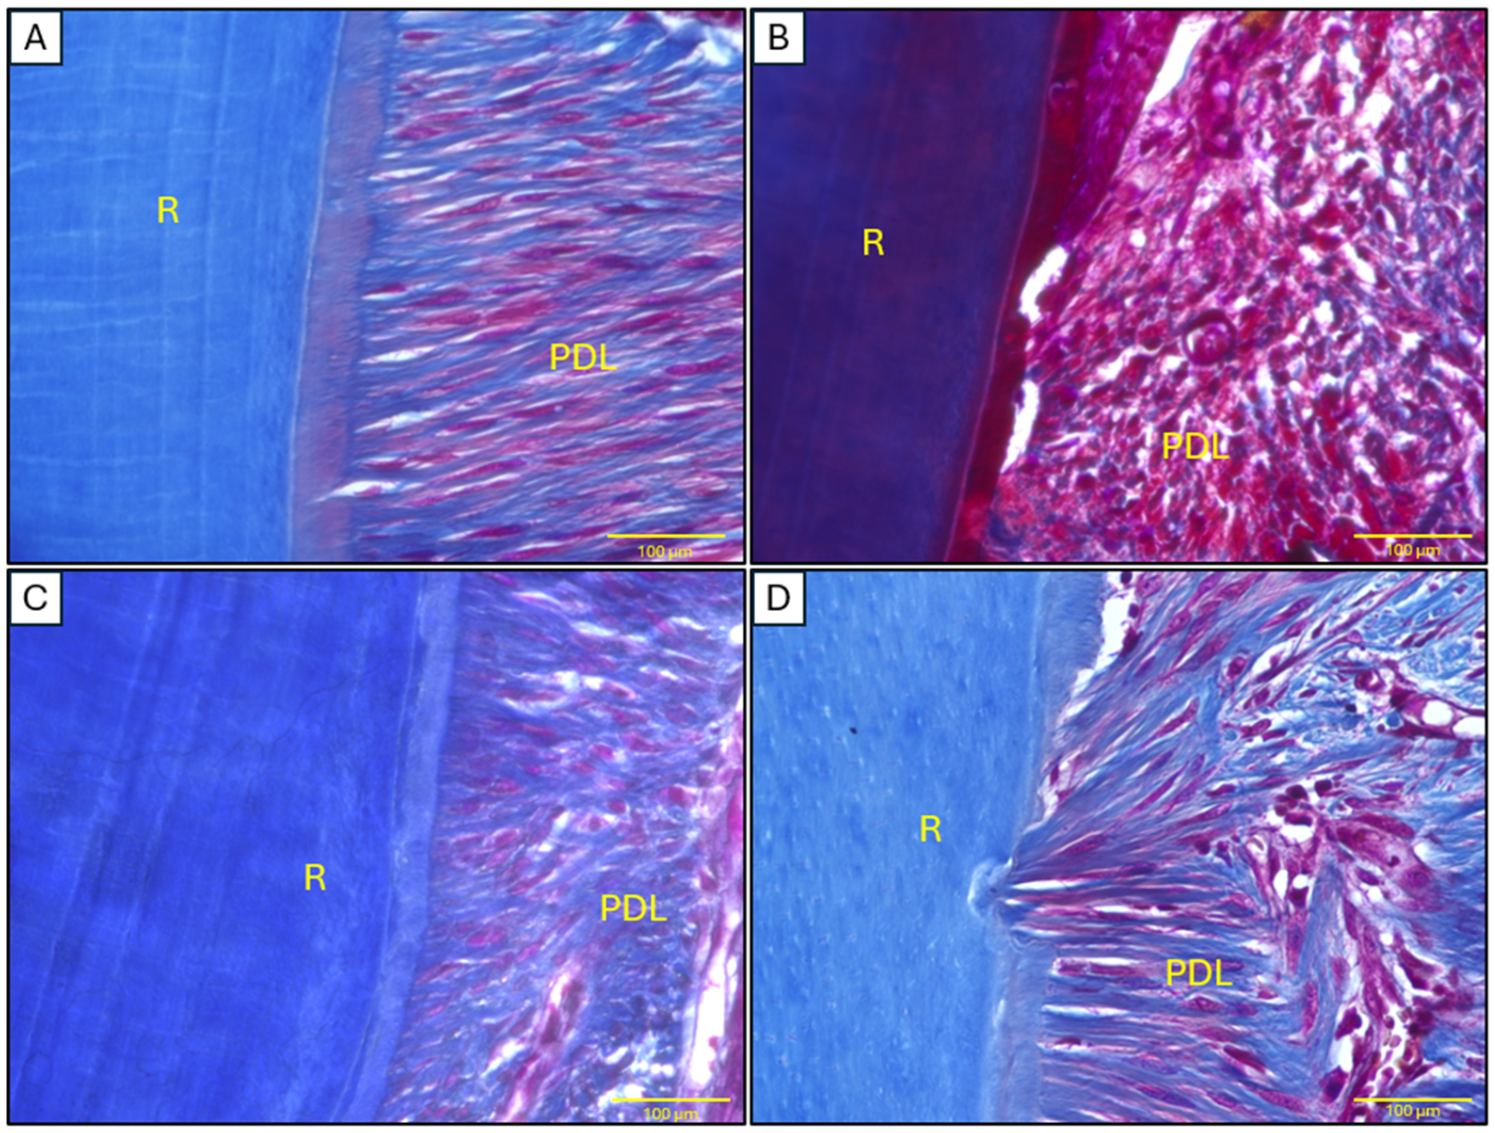

2.4. Histopathological Analysis of Mandibular Tissues

4.8.1. Mandibular Tissues

4.8.3. Staining Procedures

Masson’s Trichrome Staining